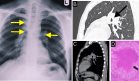

El término Takotsubo es una palabra japonesa que describe un recipiente utilizado para capturar pulpos, que se caracteriza por un cuello delgado y una base redonda. Esta imagen es similar a la observada en el ventriculograma en proyección oblicua derecha durante la sístole de pacientes con esta alteración; sin embargo, se han descrito otros patrones de afectación, siendo la afectación apical la más frecuente (81,7%).

En este caso (Sergio Velasco-Malagón, et al), se hace correspondencia a la variante más común de la CT, la apical. Aunque inicialmente se consideraba una condición benigna, se sabe que puede ocasionar complicaciones graves, y su mortalidad en la fase aguda es de aproximadamente un 5%.